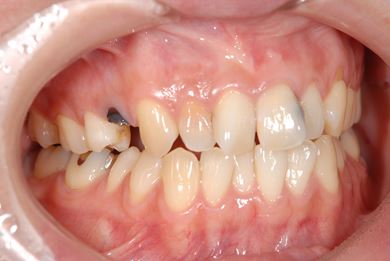

インプラント治療+セラミック治療

| カテゴリー | 【インプラント治療】【セラミック治療】 | ||||||||||||||||||||||||||||||||

| 性別/年齢 | 女性 / 30歳 | ||||||||||||||||||||||||||||||||

| 主訴 | 虫歯を治して欲しい。 | ||||||||||||||||||||||||||||||||

| 治療内容 | インプラント1本、メタルボンドセラミッククラウン1本、オールセラミッククラウン2本(オールセラミック用土台2本) | ||||||||||||||||||||||||||||||||

| 総治療費 | 703,238円 | ||||||||||||||||||||||||||||||||

| 治療期間 | 1年6ヶ月 |